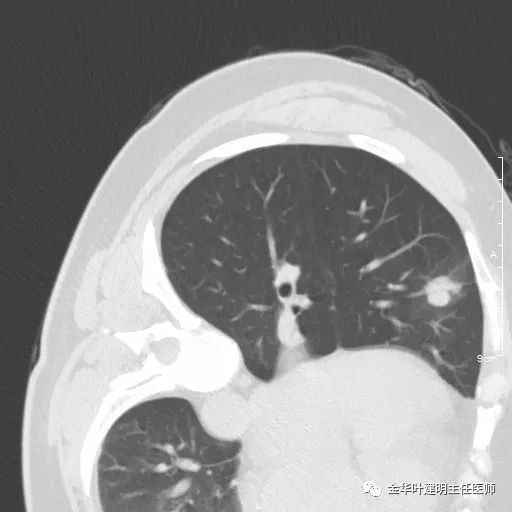

五、浸润性腺癌之粘液腺癌:

影像特征:这个病例是我在术前仅凭影像就判断其为粘液腺癌,术后确诊的。粘液腺癌表现为 实性乏收缩力、密度较均匀 的实性结节。病灶的边界一般非常清楚,没有毛刺、磨玻璃、卫星灶等,但又乏收缩力,像本例紧贴胸膜也不会有牵拉凹陷;同时病灶的密度又比较均匀(粘液成份)。良性肿瘤密度要更高些、慢性炎没有这么光整的边界,也容易有瘢痕收缩方面的影像表现、其他实性的腺癌则要有收缩力、腺泡型虽然也缺乏收缩力,但密度要不均匀些。